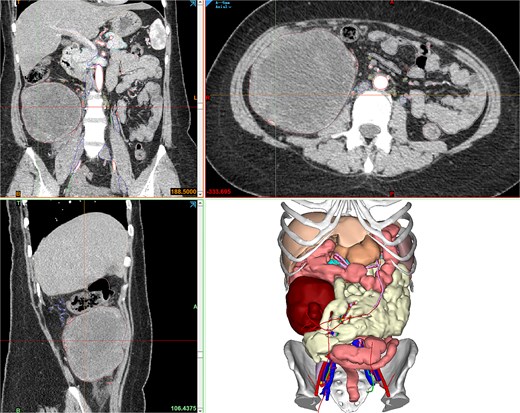

Contrast-enhanced abdominopelvic computed tomography (CT) (20 August 2024) identified a heterogeneous, hypodense mass (12 × 10.5 × 8.5 cm) arising from the ileocecal region, partially encasing the appendiceal base and colonic wall. Pelvic magnetic resonance imaging (MRI) further delineated the mass’s origin from the terminal ileum, showing adherence to the ileocolic vasculature without invasion of adjacent organs (Fig. 1). To refine surgical planning, a patient-specific 3D-printed model was generated using Mimics23 software (Materialize NV), which highlighted critical anatomical relationships, including compression of the ileocolic artery and proximity to the right ureter (Fig. 2).

Contrast-enhanced CT showing the retroperitoneal mass, and Mimics23 3D model (tumor: red; ileum; vasculature; 3-Matic®15).